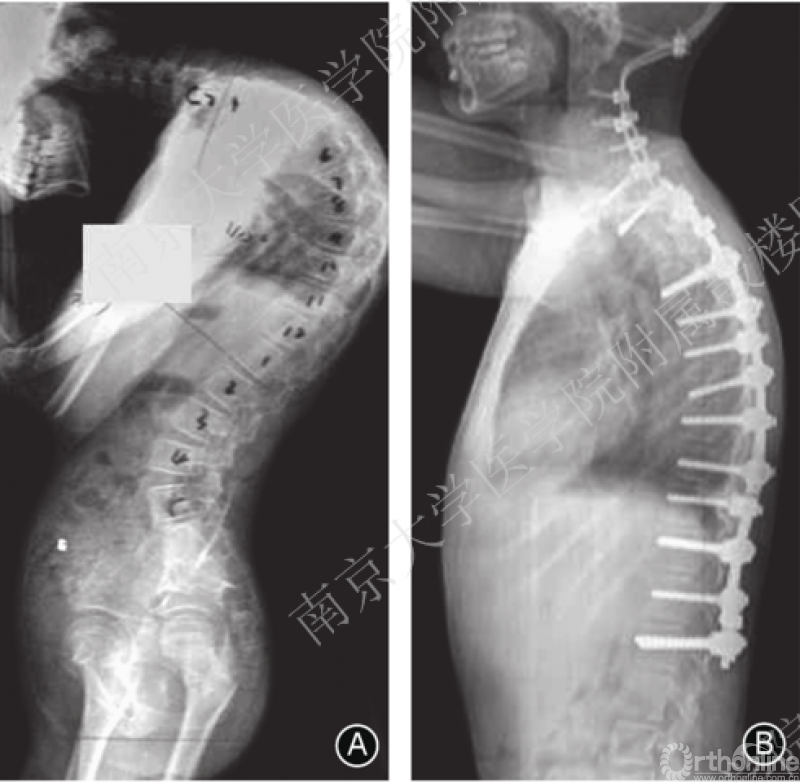

C7 PSO的优点在于生物力学稳定性强,前方组织撕裂性损伤和截骨椎脱位可能性降低,神经并发症发生率较C7-T1伸展性截骨低。适用于前纵韧带严重骨化及复杂双平面颈胸段畸形患者。手术时后路暴露截骨椎上下至少三个椎体,颈胸椎预固定后完全切除C7椎板、C6椎板下半及T1椎板上半部分,临时固定一侧,另一侧去除截骨椎内大部分松质骨,并将椎体后壁推向椎体去除松质骨后形成的腔室内并保持截骨前壁的连续性。一侧固定后同法处理对侧。椎体两侧截骨完成后,上抬患者头部造成C7压缩骨折以矫正后凸畸形。对于合并侧凸畸形者则采用不对称截骨。

单纯颈胸段和胸腰段后凸畸形可分别行颈胸段、胸腰段截骨矫正,整体后凸畸形则要考虑截骨顺序。Koller 等认为若患者有重度颈椎及轻中度胸腰椎后凸畸形可先行颈椎截骨术,术后根据患者特点决定是否行进一步腰椎截骨。Kim等认为在患者脊柱极重度后凸畸形(chin-on-pubis )时,可按颈椎、胸椎和腰椎顺序依次截骨。